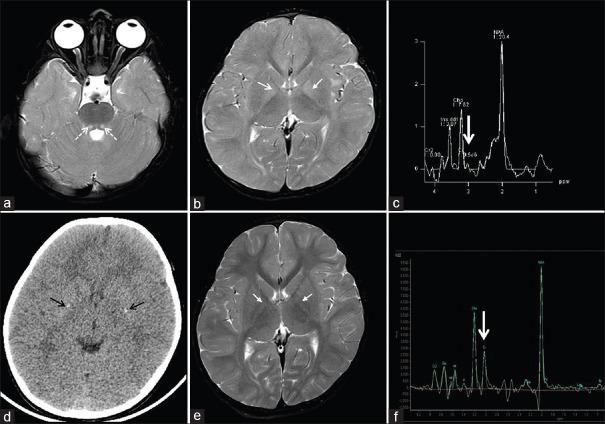

Guanidinoacetate Methyltransferase (GAMT) Deficiency, A Cerebral Creatine Deficiency Syndrome: A Rare Treatable Metabolic Disorder.